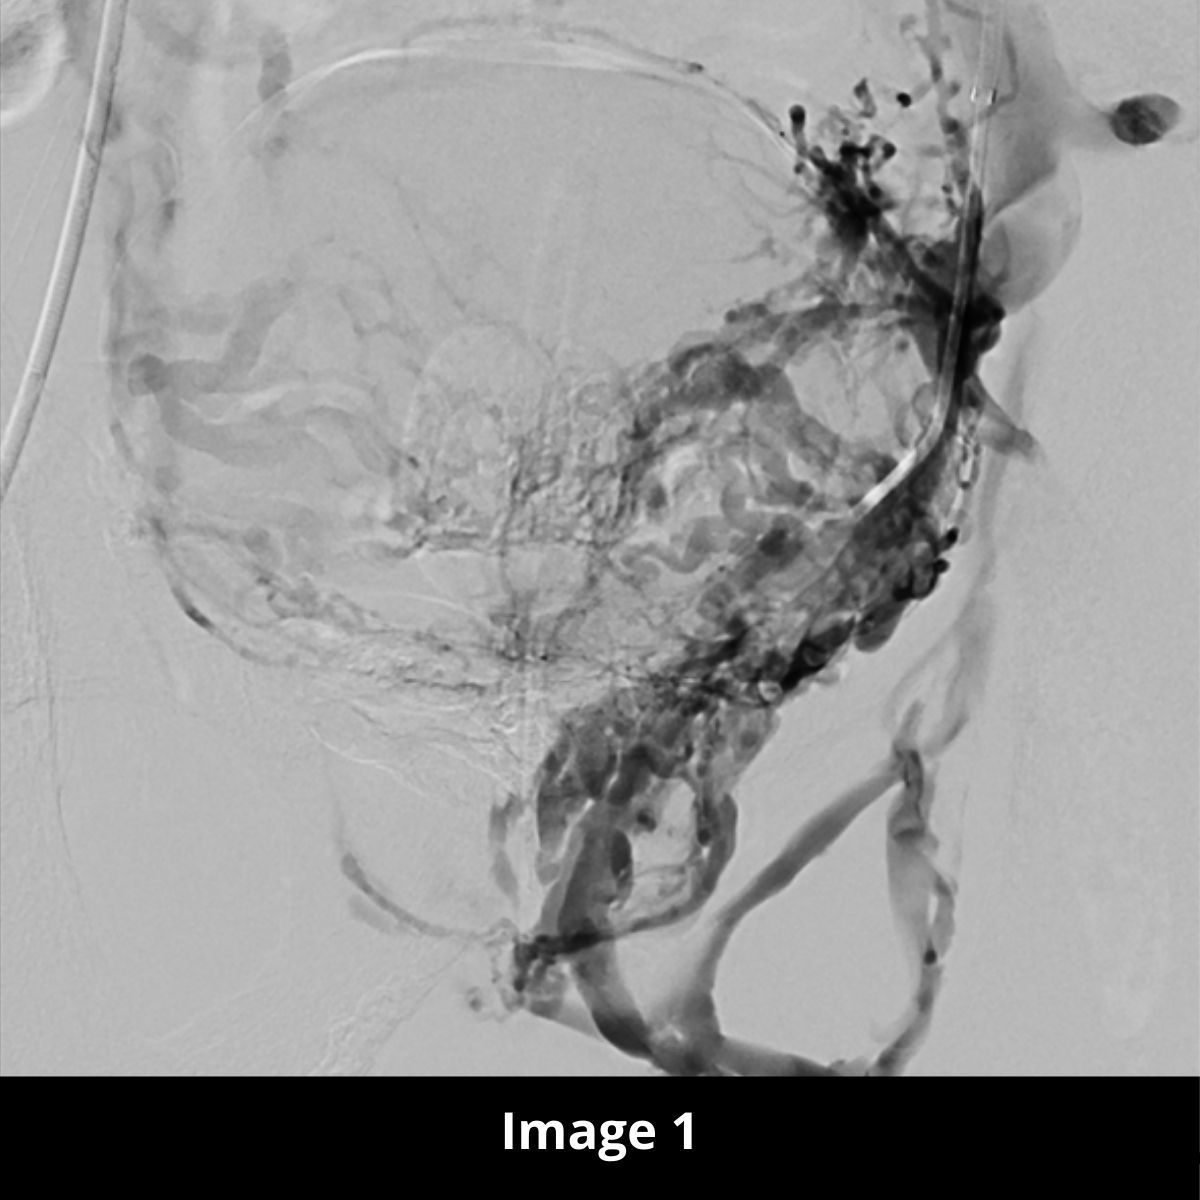

- Hypertension portale : création de shunt porto-cave par voie trans-jugulaire (TIPS), embolisation de varices d’hypertension portale, recanalisation complexe, prise en charge post-transplantation hépatique